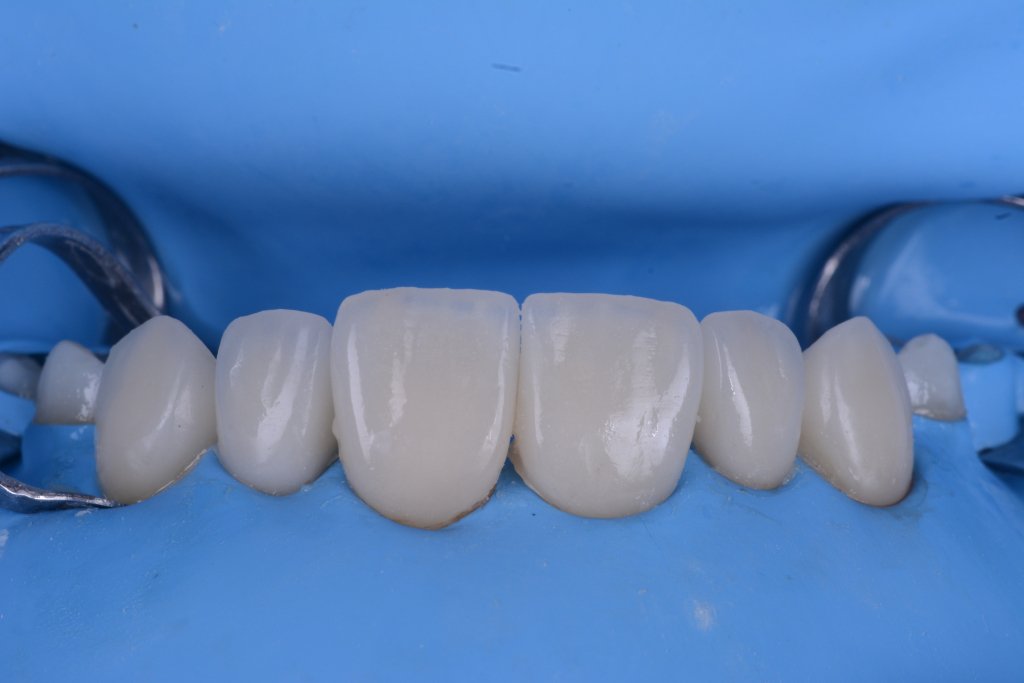

Y vamos de Azul (NIC TONE) sin linea de terminación, sufrimos el doble..no tenemos donde agarrar el Clamp y sobre todo donde realmente termina la carilla…

Voy siempre de 2 en 2, claramente cemento antes las Coronas, que me ayudaran a «clampar» y luego las carillas. Pero normalmente empiezo con los laterales que están en el medio y suelen robar el espacio a los otros

Tomaros vuestro tiempo para limpiar bien bien, no os vais a arrepentir en la vida..

Keep calm trás la retirada del Dique, esta encía volverá a su sitio (si habéis hecho bien la cirugía por supuesto).